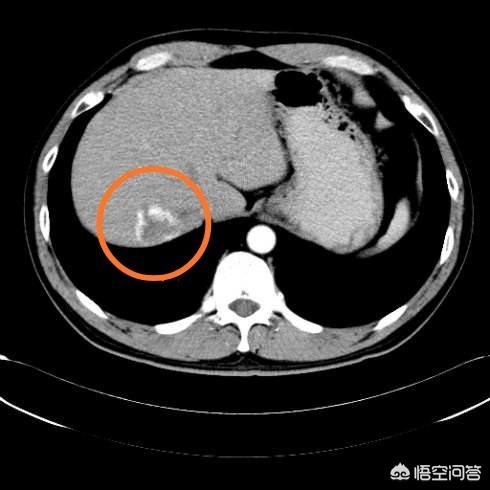

Unten ist das größte hepatische Hämangiom, das ich je gesehen habe, 16 cm groß, 54-jährige Frau, die wegen epigastrischer Schmerzen behandelt wurde.

Große Hämangiome sind solche, die größer als 5 cm sind und Symptome aufweisen, die mit einer erheblichen Kompression einhergehen, wie z. B. Schmerzen in der Leberregion, Leberfunktionsstörungen und Hämangiome am Rand der Leber. Weibliche Patienten wie die oben genannte, die Symptome haben und 16 cm groß sind, müssen aktiv behandelt werden.